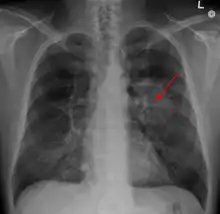

Radiographie thoracique montrant une masse parahilaire du poumon gauche